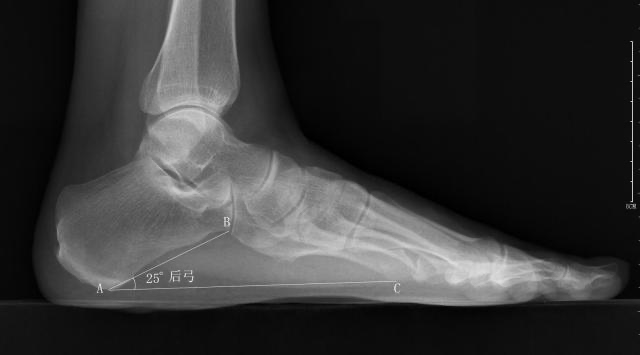

扁平足又称平足症,一种以足内侧纵弓塌陷为主要表现的足部畸形。很多平足者特别是儿童平足没有症状,也不需要治疗。少数畸形严重或症状明显者需保守或手术治疗。目前扁平足的X线测量使用不多,但是作为影像科医生,我们依然要了解掌握扁平足的X线测量方法,以备不时之需。应负重条件下摄足正侧位X线片,主要在足侧位片测量足弓的角度改变。

横弓--前弓角

-

正常值:>13°

测量方法:从第1跖跗关节最低点到第1跖骨头最低点作一条直线,再从第1跖骨头最低点到跟骨最低点作一条直线,然后测量两条直线所构成的夹角

扁平足时前弓角减小,弓形足时相反